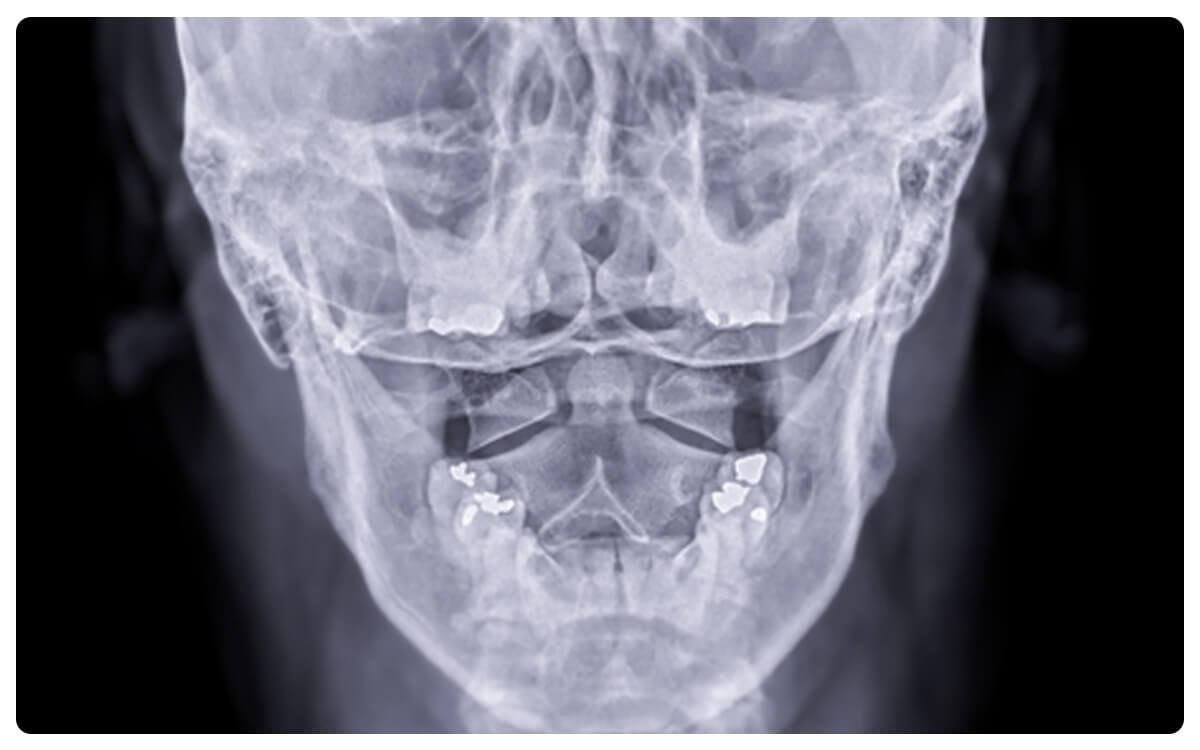

La Radiografía de Cráneo en Proyección Anteroposterior (AP) se presenta como una herramienta fundamental en la radiología diagnóstica, brindando una visión detallada y estructurada de la anatomía y posibles afecciones de la región craneal. A través de la emisión controlada de radiación, esta técnica no invasiva proporciona imágenes bidimensionales que permiten la evaluación de los huesos del cráneo y sus relaciones anatómicas desde una perspectiva frontal.

La Radiografía de Cráneo en Proyección AP desempeña un papel crucial en la detección y diagnóstico de fracturas, malformaciones óseas, lesiones y otras patologías craneales, proporcionando información valiosa para la toma de decisiones clínicas informadas y el manejo adecuado de las afecciones relacionadas con el cráneo.